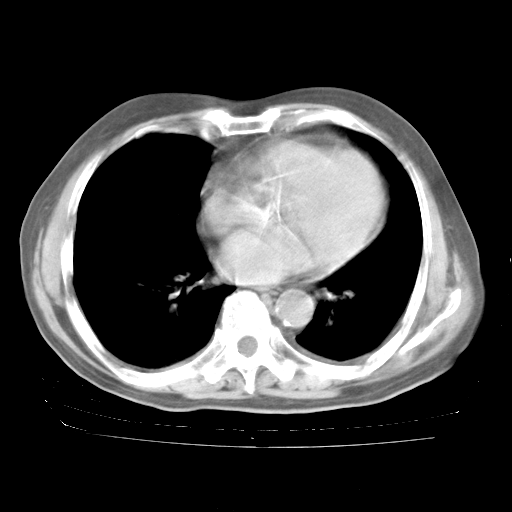

4月28日肺部CT——再次出现类似去年5月9日——透光度降低,“间质性”改变。

4月28日肺部CT